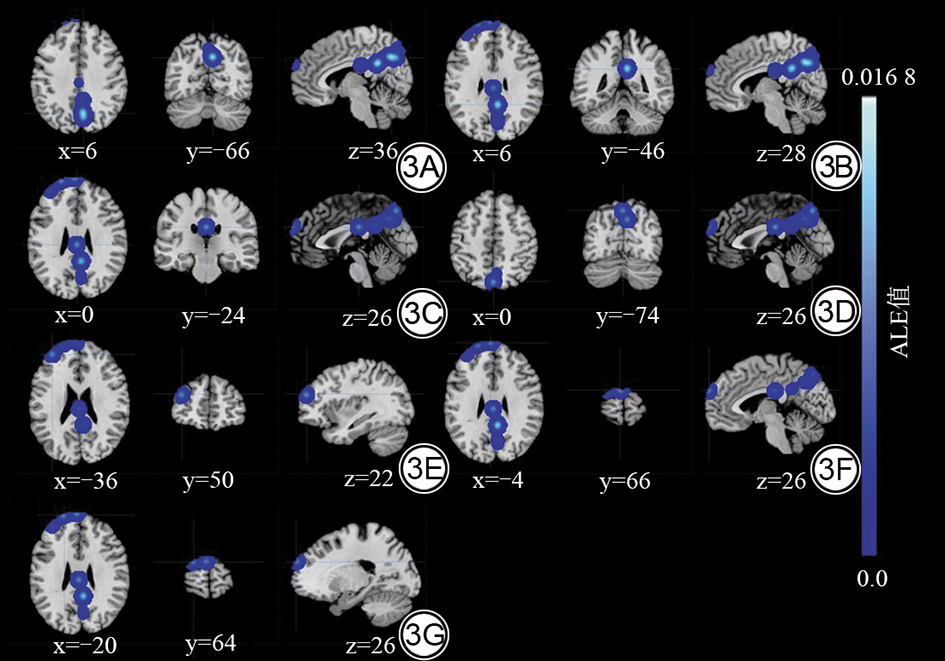

ALE元分析结果显示:与HCs相比,BPD患者在左侧豆状核、左侧海马旁回及双侧楔叶表现出自发脑活动增高(表2图2);而在右侧楔叶、右侧后扣带回、左侧扣带回、左侧楔前叶、左侧额中回及左侧额上回表现出自发脑活动减低(表2图3)。为更直观地展示上述结果,还绘制了三维脑表面渲染图(图4)。

图3  BPD患者相对于HCs脑自发活动减低脑区的ALE元分析结果。右侧楔叶(BA 7,3A)、右侧后扣带回(BA 23,3B)、左侧扣带回(BA 23,3C)、左侧楔前叶(BA 7,3D)、左侧额中回(BA 9,3E)及左侧额上回(BA 9,3F和3G)活动减低(cFWE,P<0.05)。BPD:边缘型人格障碍;HCs:健康对照;ALE:激活似然估计法;BA:Brodmann分区。

Fig. 3  ALE meta-analysis results showing decreased spontaneous brain activity in BPD patients compared to HCs. Decreased activity is primarily observed in the right cuneus (BA 7, 3A), right posterior cingulate cortex (BA 23, 3B), left cingulate gyrus (BA 23, 3C), left precuneus (BA 7, 3D), left middle frontal gyrus (BA 9, 3E), and left superior frontal gyrus (BA 9, 3F and 3G) (cFWE, P < 0.05). BPD: borderline personality disorder; HCs: healthy controls; ALE: activation likelihood estimation; BA: Brodmann area.